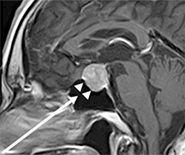

下垂体腫瘍の治療法としては、薬物によって腫瘍の縮小やホルモンの調節を行う内科的治療と、手術により取り除いてしまう外科的治療があります。残念ながら薬物による腫瘍の縮小が期待できるものは、現時点ではまだ成長ホルモンとプロラクチンを作っている腫瘍のみです。その他の腫瘍の場合や薬物の効果が不十分な場合などは外科的手術が必要になります。幸いにも他の脳腫瘍とは異なり、下垂体腫瘍は頭蓋骨の一部を切りとることなく、図2の矢印の方向に鼻の穴を経由して行う方法が一般的です。ただ、手術用顕微鏡を使用していた時代は鼻の穴を経由するためその視野は狭くて約1.5 cmほどしかなく、完全に取り除けない場合もありました。しかし、当科では平成23年7月より神経内視鏡を使用するようになり、図2の矢印の部分までそれを挿入することで、顕微鏡より明るく広い視野で手術ができるようになりました。その結果、径が2.5cm以上の腫瘍の摘出率が改善しました。図3は図2の手術後のMRIで、腫瘍が完全に取り除かれています。また、この方法ですと手術時間も3時間程度で出血量も少なく、患者さんの術後の負担は頭蓋骨を取り除く場合より格段に軽く、翌日から歩いたり食事を摂ったりすることも可能です。手術により起こりうる合併症は、正常の下垂体の機能が低下したり、尿量が増えたりすることです。そのため、一次的にはそれらを調節するホルモンの補充が必要になる場合もありますが、大部分は一次的なもので数週から数ヶ月で回復することがほとんどです。

図3